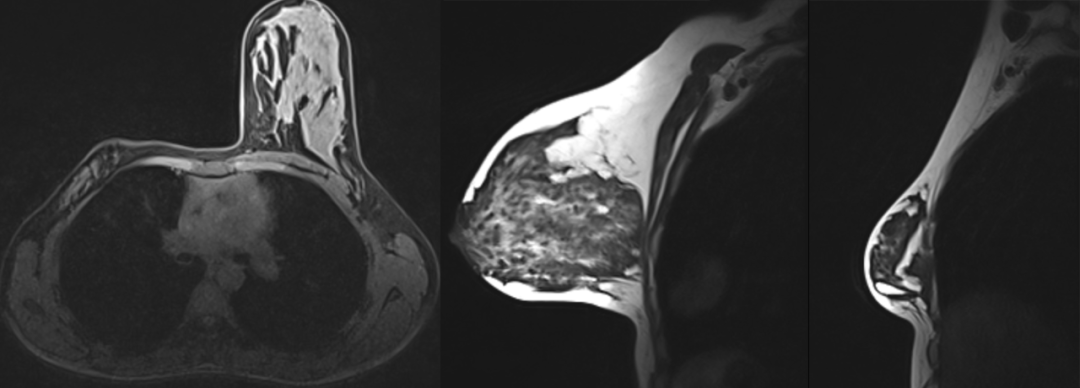

病例 1:左侧胸大肌及胸小肌缺如,并左侧胸腔积液

病例 2:右侧胸大肌和胸小肌缺如,右侧乳房明显缩小